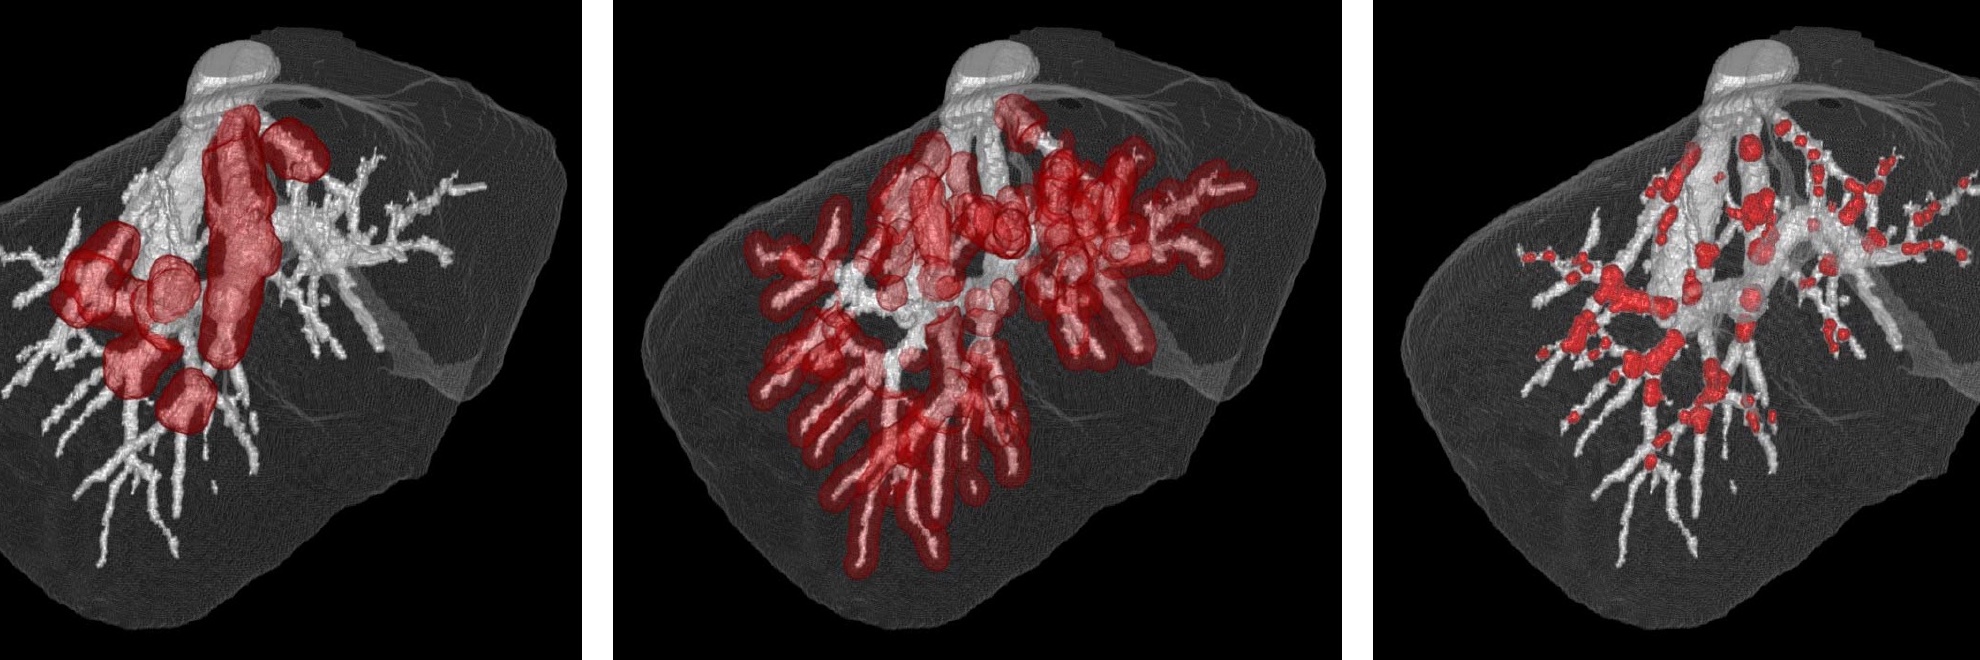

Les champs d'expertise numérique de l'équipe reposent sur les champs suivants : intelligence artificielle, image, analyse exploratoire de données, observabilité des données, analyse multiéchelle, morphologie mathématique, topologie discrète, filtrage spatio-fréquentiel, analyse dynamique, classification, décision, mesure de similarité, détection de changements, modélisation statistique.

Les champs d'expertise clinique de l'équipe reposent sur les modalités suivantes : imagerie par résonance magnétique (IRM), scanner (TDM), artériographie, imagerie nucléaire (TEP, TEMP), électroencéphalographie (EEG), échographie, imagerie préclinique (synchrotron). Les domaines cliniques privilégiés sont la néonatologie, la cancérologie, la neurologie, la radiologie, l'endocrinologie, l'urologie, l'histopathologie.